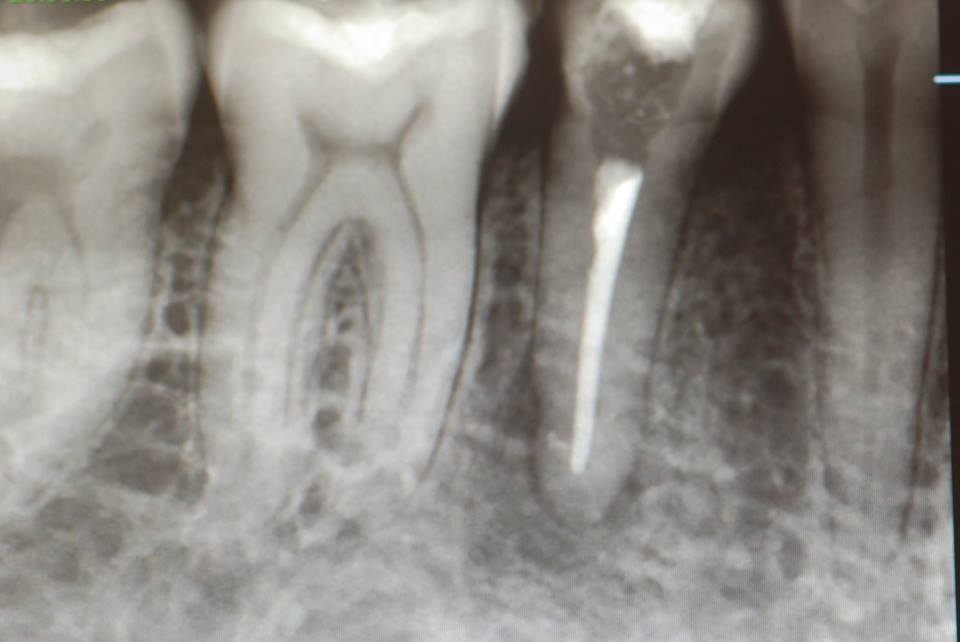

レントゲンと話の内容から、食いしばりや歯ぎしりによるものではなく、単純にぶつかる歯が少ないので、その時に前歯のところで何か硬い物などを噛んだために外傷性の痛みが来たのではないかという判断でした。炎症でもないので、奥歯にマウスピースなどを入れて前歯を当たらなくした後に、症状が緩解したら、反対咬合という上下の前歯の関係を簡単な小矯正で変更した方がいいという診断と治療方針の提案で解決しました。

2、67才、女性、主訴は噛みあわせがおかしい。

矯正している。左の上下の6才大臼歯を保険の金属冠から都内の某所でジルコニアという硬いセラミック?冠に変えてからおかしくなっていったそうです。担当の歯科医師は削ったりしてどちらの歯も当たっていないぐらい削っているに違和感が取れないという主訴です。兵庫県の先生からの相談でした。